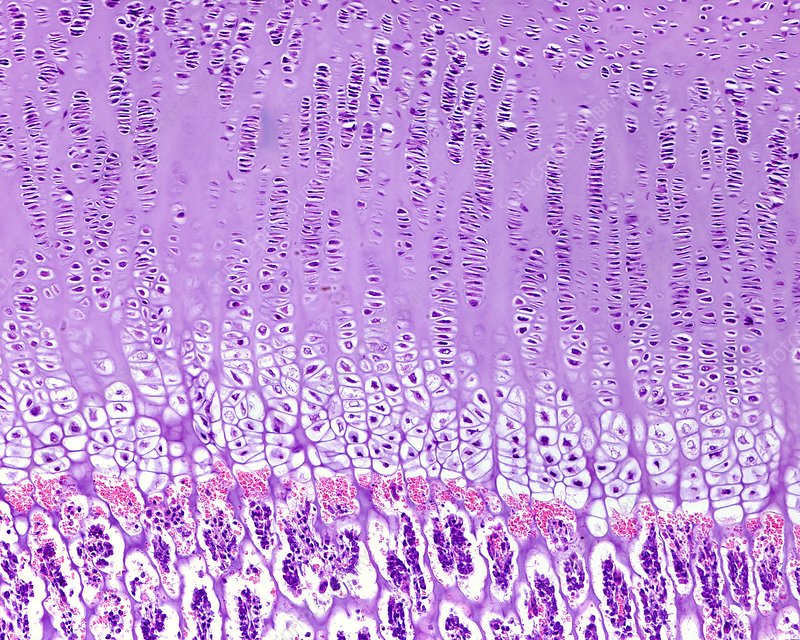

what are the zones in endochondral ossification

zone of reserve cartilage

zone of proliferation

zone of hypertrophy

zone of calcification

where does endochondral ossification take place on a long bone

at the physis